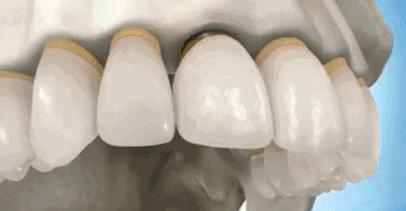

2,省略种植步骤。种植体手术一般分为一期和二期手术,在一期种植体植入后会先安装临时的愈合基台,在二期安装永久基台和修复牙冠,但有些低价种植手术会省略一些必要的步骤,这给患者今后的愈合留下了极大的隐患,也有可能会降低患者之后种植体的使用体验。

2,术后慢性炎症。这个可能是由于手术人员操作不当或者是种植体材料不合格,导致基台与种植体连接不当或穿龈过少,这很容易造成种植区域的卫生清洁问题,在术后引起患者手术区域的慢性炎症。